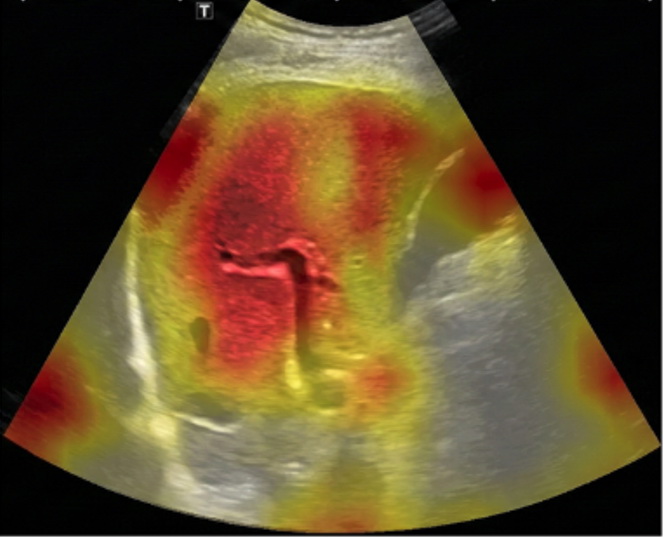

SmartLiva ทำงานเหมือน “อัปเกรด” จากภาพอัลตราซาวด์ขาวดำธรรมดาให้กลายเป็นผลวินิจฉัยที่อ่านง่ายและแม่นยำ โดยแพทย์อัปโหลดภาพผ่านเว็บได้ทั้งบนคอมพิวเตอร์หรือแท็บเล็ต จากนั้นระบบจะช่วยปรับภาพให้ชัดขึ้น คัดเฉพาะบริเวณเนื้อตับที่ต้องวิเคราะห์ และทำให้ภาพดูเข้าใจง่ายขึ้นด้วยการไฮไลต์เป็นสี (เช่น ตับเป็นสีแดง ไขมันเป็นสีเหลือง) เพื่อให้เห็นความผิดปกติได้ทันที โดย AI จะทำการประเมิน 3 เรื่องพร้อมกัน คือ ประเมินระดับพังผืด/ความแข็งของตับ (F0–F4) ตรวจหาความผิดปกติของเนื้อเยื่ออย่างถุงน้ำหรือมะเร็งตับ และตรวจหาพยาธิใบไม้ตับ ซึ่งตัว AI จะทำการประมวล วิเคราะห์ และสรุปผลออกมาเป็นรายงานพร้อมภาพประกอบและคำอธิบายที่คนทั่วไปเข้าใจได้ โดย AI ทั้งหมดถูกฝึกฝน (Train) ด้วยฐานข้อมูลภาพอัลตราซาวด์กว่า 50000 ภาพ จากโรงพยาบาลชั้นนำ อย่างโรงพยาบาลขอนแก่น โรงพยาบาลจุฬาลงกรณ์ และโรงพยาบาลรามาธิบดี